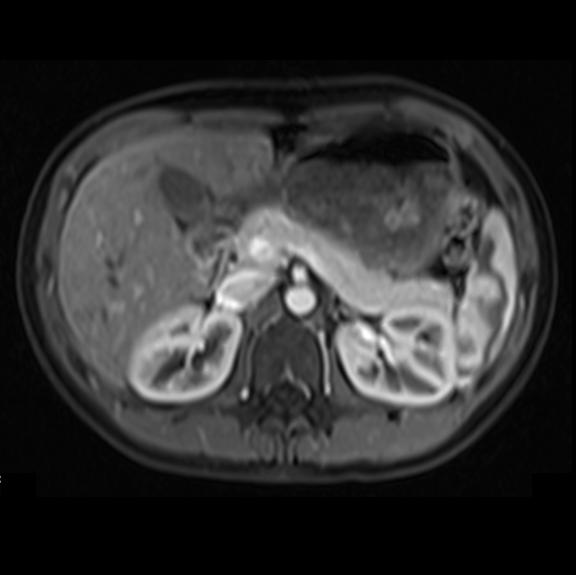

From www.researchgate.net

MRI of a pancreatic carcinoma following surgery. Eight days following Imaging Techniques For Pancreatic Cancer Multisection ct scanning is generally accepted to be the first line of investigation in a patient with suspected. In this review, we aim to. Our study investigates the current role of pancreatic imaging, including computed tomography (ct), magnetic resonance imaging. The most important types of imaging for the detection of pancreatic cancer. Understanding the stage (severity) of the tumor is. Imaging Techniques For Pancreatic Cancer.